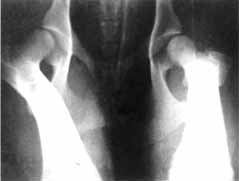

| HD -

Frühdiagnose, G-Wurf im Alter von 9 Wochen (Röntgenkontrolle ohne Narkose) Alle Röntgenbilder zeigen bereits im Alter von 9 Wochen sehr gut ausgeprägte Hüftgelenke. Die Kugel liegt gut in der Pfanne. Es gibt damit keinen Hinweis für lockere Hüften, die später zur HD führen kann. Probleme durch mittlere u. schwere HD können damit ausgeschlossen werden. |

Nachkontrollen im Alter vom 17. - 18. Lebensmonat haben

ergeben, daß sich der HD-Durchschnitt unseres G-Wurfes zwischen 0 - 1

bewegt. Die Röntgenbilder von der 9. Lebenswoche zeigen schon

charakteristische Merkmale der Röntgenbilder vom 17. - 18. Lebensmonat.

Fütterung u. Haltung waren so optimal, daß sich die Gelenke mit

zunehmenden Alter nicht negativ entwickelten. Ein Wert von HD-0 für alle

Welpen ist allerdings kaum zu erreichen. Da im VDH/DDC immer noch Doggen mit HD-2 zur Zucht zugelassen

werden, wird das Thema HD wohl weiter aktuell bleiben. Die Früherkennung von HD durch Röntgendiagnose ist für uns ein ergänzendes Mittel um unsere Zuchtlinie HD-frei zu halten. (HD-1=Verdacht oder Übergangsstadium) |

Bild 1 zeigt trotz schlechter Lagerung eine Differenz im Norbergwinkel zwischen der linken und rechten Hüfte der Hündin. Wir wiederholten im Alter von 17,5 Monaten die Aufnahme der Hüfte. (diesmal unter Vollnarkose) Es zeigte sich, daß die linke Hüfte einen Norbergwinkel von 100° hatte. An der rechten Hüfte wurden 105° gemessen. Der Gelenkspalt und die Gelenke waren vorbildlich. Die Hündin wurde demnach mit HD-1 also Übergangsstadium eingeschätzt.

Bild 2 zeigt bereits im Alter von 9 Wochen ein absolut vorbildliches Röntgenbild der Hüfte. Die Hündin wurde im Alter von 17 Monaten ebenfalls geröngt. Sie wurde als HD-frei bewertet. (HD-0)

Im Alter von 9 Wochen läßt sich meiner Meinung nach sehr gut die Lagerung des Gelenkkopfes in der Pfanne beurteilen. Desweiteren sind bereits Rückschlüsse auf den zu erwartenden Norbergwinkel möglich. Eine Einschätzung des Gelenkspaltes halte ich für fragwürdig.